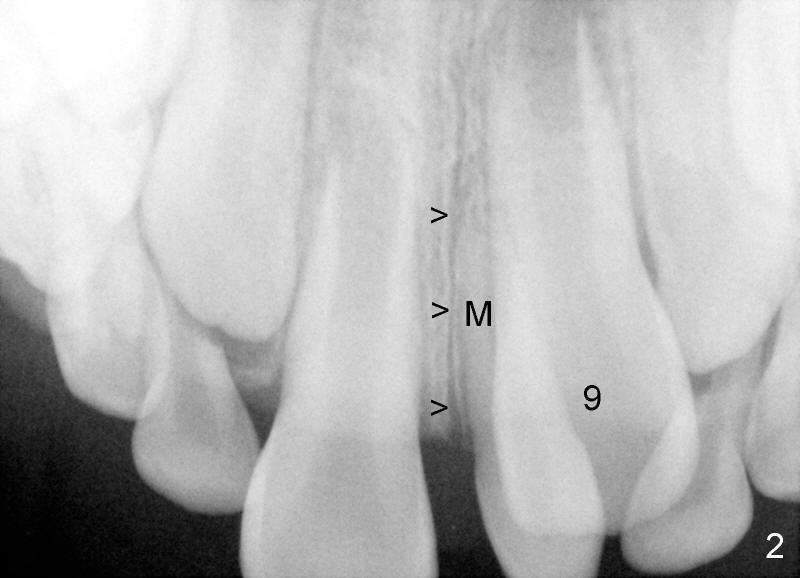

Crown of mesiodens (M) may be oriented toward apically (Fig.1), coronally (Fig.2) or palatally (Fig.4 axial section of CBCT). A common characteristic of mesiodens is that it does not cross midline suture (Fig.1,2 black arrowheads, Fig.4 white arrowheads), although it can push and deform midline suture (Fig.1,2,4 red arrowheads).

The mesiodens in Fig.1 should be removed because its potential upward growth may interfere with #8 eruption. The PA is taken when the patient is 5.5 years old. The surgery is done when the patient is 6 years old. Initially the mesiodens is difficult to locate through buccal approach. It appears that CBCT is required prior to surgery to reduce surgical trauma.

How does this happen? Here is a hypothesis. Fig.6A diagrammatically shows the developing premaxilla, which consists of the right and left portions, separated by the midline suture (solid arrow) and the incisal canal (I). As well-known, the developing deciduous incisor tooth buds (A, B) give rise palatally to permanent tooth buds (1,2), respectively (open arrows). For unknown reasons, the developing permanent central incisor tooth bud produces medially an extra tooth bud (mesiodens, green circle in Fig. 6B). The cortices of the developing midline suture appears to be a barrier for the developing mesiodens. Unlike deciduous or permanent teeth, the development mesiodens apparently does not have its definitive growth pattern (probably due to its absence of deciduous precursor). It may grow upward (Fig.1), downward (Fig.2) or palatally (Fig.4,6C) along suture cortex.